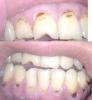

АнтиОрбит Опубликовано 30 апреля, 2009 Автор Поделиться Опубликовано 30 апреля, 2009 Что у вас- вредная привычка,которая привела к дефекту(семечки возможно)+ проблемы с прикусом Я вобще-то по поводу коричневых разъедов-ковыряя их,чувствую,что отсутствует эмаль-часть зуба и десны поднят вверх и вниз на нижней челюсти соответствено.Эти коричневые наросты не удаляются при отбеливании эмали,гигеенист после неудавшегося отбеливания на мой вопрос-так что,это не камень?Сказал-кариес.Эта шняга реагирует на температуру-такое ощущение будто зуб чешется.Коричневая шняшка на зубах-это что? Ссылка на комментарий

Д.С. Опубликовано 30 апреля, 2009 Поделиться Опубликовано 30 апреля, 2009 Это далеко не ребус.Банальный пришеечный кариес.Причины, как и писали коллеги выше:проблемы с прикусом, вредные привычки, плохая гигиена Ссылка на комментарий

Bier Опубликовано 30 апреля, 2009 Поделиться Опубликовано 30 апреля, 2009 там рецессии, я бы обработал полости и если там не пульпит - пересадка подслизистого лоскута с нёба + эмдогейн с коронарно смещенным лоскутом.По последним данным, даже цемент корня несколько восстанавливается. Ссылка на комментарий

Bier Опубликовано 30 апреля, 2009 Поделиться Опубликовано 30 апреля, 2009 не могу вникнуть в суть термина-рецессия...понятно,что отклонение.А так я записал,вдруг храбрости наберусь,пойду к стоматолагу и продекларирую ему.Может и правда,без бура можно обойтись.А пульпит?Как бы Вы узнали,есть он или нет?Я почему пломбы не хочу,в друг заметно будет?Это ж как налет белый будет похоже.Хотя,в моем случае,чем коричневый налет лучше?Неохота все зубы сверлить,тем паче они чувствительные.А чем бы Вы полости обработали?я так понял-этот пришеечный кариес обработали бы?рецессия - десны отошли от зубов наверх на в. челюсти и вниз на н.ч. (оголение шеек зубов)На шейках у вас кариес, обработать - значит взять бор и спилить все это. Если при этом полость получится не очень глубокая - закрыть рецессии без установки пломбы.Если полость будет глубокая, то придется депульпировать зуб и делать на него коронку.если все оставить как есть, кариес будет углубляться и в итоге зуб сломается. Ссылка на комментарий